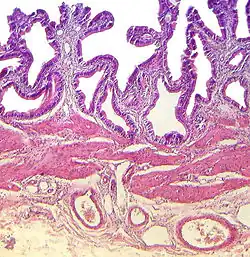

Die etwa 0,4 cm dicke Wand des Hohlorgans ist histologisch dreischichtig gegliedert. Von innen (Lumen) nach außen unterscheidet man eine Tunica mucosa, bestehend aus Epithel und einer Lamina propria, eine Tunica muscularis und eine Tunica serosa.

Die Tunica mucosa (Schleimhaut) besteht aus einer lumenwärts gelegenen Schicht Oberflächenepithel und einer darunterliegenden Bindegewebsschicht mit Blutgefäßen, der Lamina propria. Bedingt durch die Farbe der Galle ist die Schleimhaut grün gefärbt. Sie ist zu Falten aufgeworfen, die bei zunehmender Füllung geglättet werden. Die Aneinanderlagerung von Falten führt zu so genannten „Schleimhautbrücken“, die charakteristisch für das histologische Präparat einer Gallenblase sind. Gelegentlich vorkommende Krypten werden Rokitansky-Aschoff-Krypten genannt. Das Oberflächenepithel besteht aus so genannten Hauptzellen, ist einschichtig und zeichnet sich durch eine große Anzahl von Mikrovilli aus. Die Zellen sind durch Nexus, Desmosomen und Schlussleisten miteinander verbunden. Funktion der Hauptzellen ist der Entzug von Wasser zur Konzentrierung der Galle und die Produktion von Schleim zum Schutz des Organs vor Gallenbestandteilen. Bei einigen Säugetieren (Fleischfressern, Paarhufern) besitzt die Schleimhaut im Bereich des Gallenblasenhalses muköse Drüsen, die Muzine synthetisieren.[5] Bei chronischen Entzündungen kann die Anzahl dieser Drüsen erhöht sein.

Die mittlere der drei Schichten, die dünne Tunica muscularis, besteht aus glatter Muskulatur in scherengitterartiger Anordnung und vereinzelten bindegewebigen Anteilen. Die Schicht ist für die Entleerung des Organs notwendig.[5]

Die außen liegende Tunica serosa besteht, außer an der der Leber anliegenden Stelle, wo eine Tunica adventitia ausgebildet ist, aus dem Epithel des Peritoneums und darunter liegendem Bindegewebe. Diese Schicht führt neben Nervenfasern auch Blutgefäße.